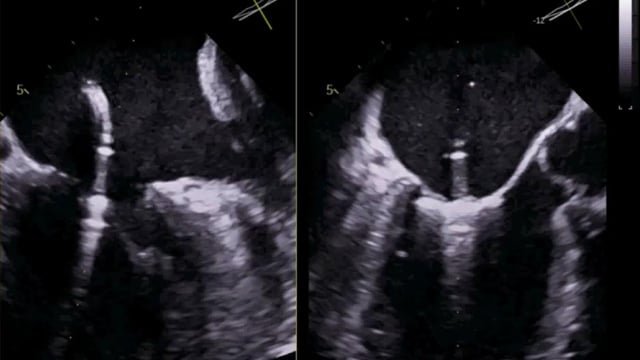

Tricuspid valve - How to evaluate?

This session offers a detailed evaluation framework for the tricuspid valve, encompassing clinical decision-making, anatomical assessment with 2D and 3D imaging, quantification of regurgitation, and differentiation of secondary and device-related tricuspid regurgitation, supported by advanced imaging software techniques.